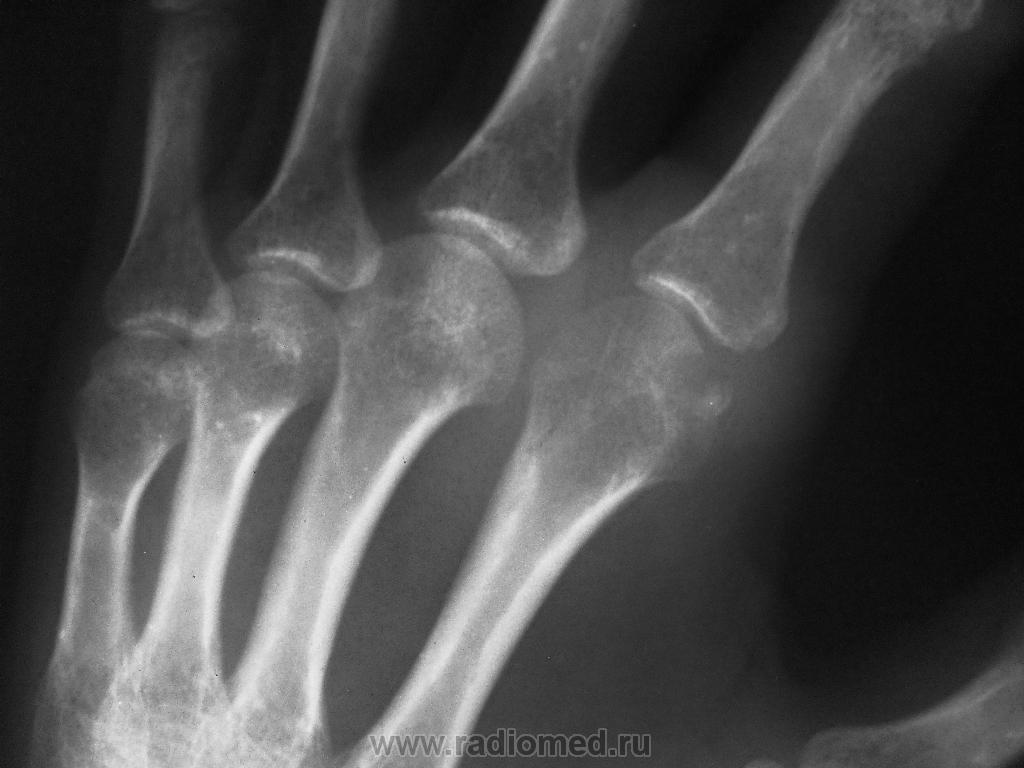

Остеоид-остеома? Женщина 46 лет.

Направлена врачом общей практики с диагнозом: посттравматический ДОА? 2-го пястно-фалангового сустава. Травма около месяца назад. Прошу высказать Ваше мнение.

остеоид-остеома-очаг деструкции костной ткани с четкими контурами и участком некроза в центре...я этого не вижу.Но вот какая-то фрагментация головки 2ой пястной кости,может,что-то из области остеохондропатий?или застарелых переломов?

Да мне в головке 2-й пястной кости это и видится...

я имела в виду,что по определению не подходит, да и вообще не тянет.Сама головка кости в месте дефекта с довольно четкими склерозированними контурами-уже не острый процесс (если,например,думать о асептическом некрозе)...надо подумать,посмотреть картинки))

Тут Татьяну Валентиновну заинересовать-позвать…, остальные много не прояснят. Мне травматическое повреждение крупной кисты или также травматический остеомиелит с отторжением секвестра (менее вероятен). Об асептическом некрозе (бывает ли в таких мелких костях?) вспомнилось….

Kat, а разве для остеоид-остеомы не характерен четкий склерозированный контур?)) Да и острым процессом эту патологию назвать трудно. Просто картинка не совсем типичная, я сомневаюсь, поскольку мне лично остеоид-остеома не попадалась еще. На кисту и добавочную кость, на мой взгляд, не похоже - некроз фрагментика у меня сомнений не вызывает, очень плотный.

вот это я и пыталась рассмотреть)) тогда должон быть асептический некроз.Еще мысль о хр.остеомиелите. А остеод-остеомы не так выглядят,даже если бы она была в головке кости. Предложение кисты-это уже фантазия от нечеткого вИдения.

Все правы -посттравматический асептический некроз(деформирующий остеоартроз).